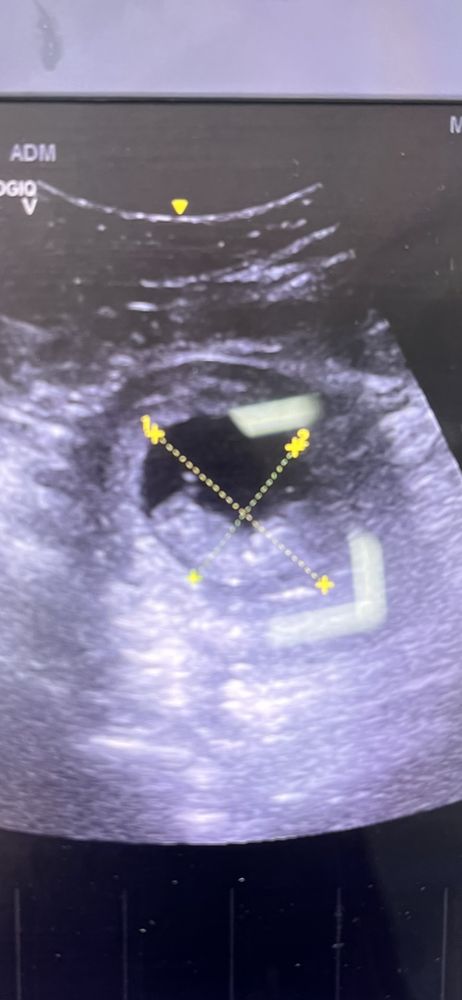

Виктория, ИзображениеЭто 10 недель, он просто лежит и уже смахивает на человека , но не видно хорошо пальчиков и всего остального. Изображение Это с приложения 9 недель , вы видите пальчики на руках??? Я с вами спорить не буду , более информативно смотреть когда больше 11

Виктория, в ту беременность , я делала на ранних сроках почти каждую неделю , из-за отслойки, именно гибель плода никак не связана, с узи, это уже было на более позднем сроке. В эту беременность из-за страха , делала на 5,6,9,11,12 ну и сам скрининг. Аппараты действительно все разные . В одном вообще мне намерили ктр на 9 недель , хотя у меня было 11. Но всех этих малышариков я все время смотрела и самое более похожее прям мини человечек это 11 недель , как по мне. Спасибо, вам тоже всего доброго.